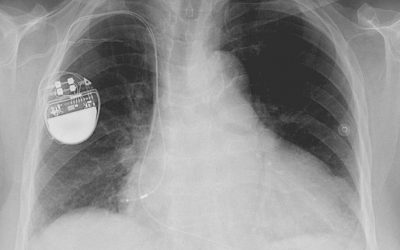

- Cardiac device implantation

Pacemaker Implantation Procedure

For every million people in the UK, around 560 have a pacemaker implanted for the first time each year. If you or someone you love needs a pacemaker, then it can be scary and overwhelming news. Learning more about the pacemaker implantation procedure can take away...